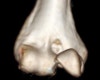

활차 골절(Trochlea fracture) : 팔을 짚고 넘어진 뒤 활차(trochlea)가 부러졌어요

활차(trochlea)에 생긴 골절을 말합니다.